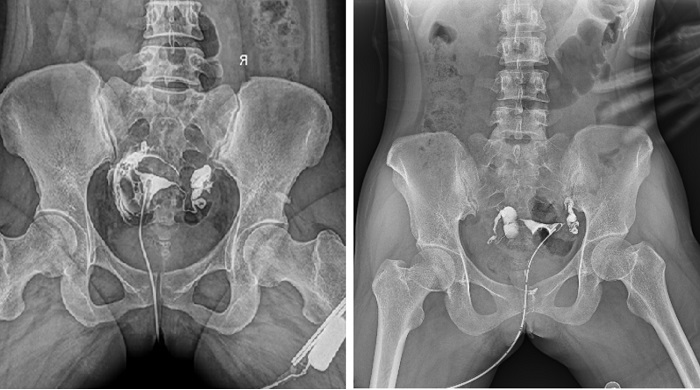

輸卵管造影檢查可根據(jù)造影劑在輸卵管及盆腔內(nèi)的顯影情況了解輸卵管是否通暢、阻塞部位及宮腔形態(tài),是超聲、CT、核磁、宮腔鏡、腹腔鏡、輸卵管鏡等所無(wú)法替代的。作為目前普放領(lǐng)域最先進(jìn)的影像設(shè)備,多功能動(dòng)態(tài)DR進(jìn)行子宮輸卵管造影檢查,大大超越了過(guò)去的檢查技術(shù),更加精準(zhǔn)、便捷、高效。

相較于傳統(tǒng)胃腸機(jī),動(dòng)態(tài)DR矩形采集面積大,一次曝光即可顯示整個(gè)盆腔,大幅減少觀察時(shí)間,可控的瞬時(shí)照射避免受檢者吸收過(guò)多的X線,對(duì)育齡期女性的檢查尤為重要。毫秒級(jí)時(shí)間內(nèi)高清點(diǎn)片,可以在造影劑流動(dòng)的過(guò)程中完成拍片,抓拍到關(guān)鍵圖像,更加清楚地了解到管腔的具體通暢情況及堵塞部位,對(duì)檢查及診斷有非常重要的價(jià)值。

子宮輸卵管造影

此外,應(yīng)用動(dòng)態(tài) DR 進(jìn)行子宮輸卵管造影,還可以在加壓推注下,使部分輸卵管輕、中度堵塞的患者得以通暢,起到一定的治療作用。